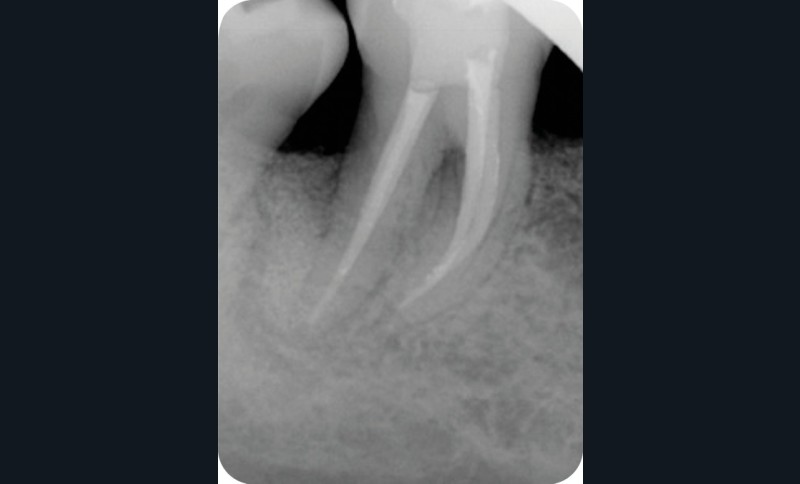

Radiographie contrôle à 4 ans |

2. Exemple de prise en charge d’une lésion endo-parodontale sans atteinte de l’intégrité radiculaire, chez un patient atteint de parodontite, de grade 3 (poche parodontale profonde sur plus d’une surface dentaire). Le traitement endodontique est réalisé dans un premier temps. Après réévaluation à 6 mois, une contention a été placée et une thérapeutique parodontale complémentaire a pu être réalisée (surfaçage et mise en place de matériaux de comblement). La maintenance parodontale est effectuée régulièrement afin de maintenir le résultat obtenu.